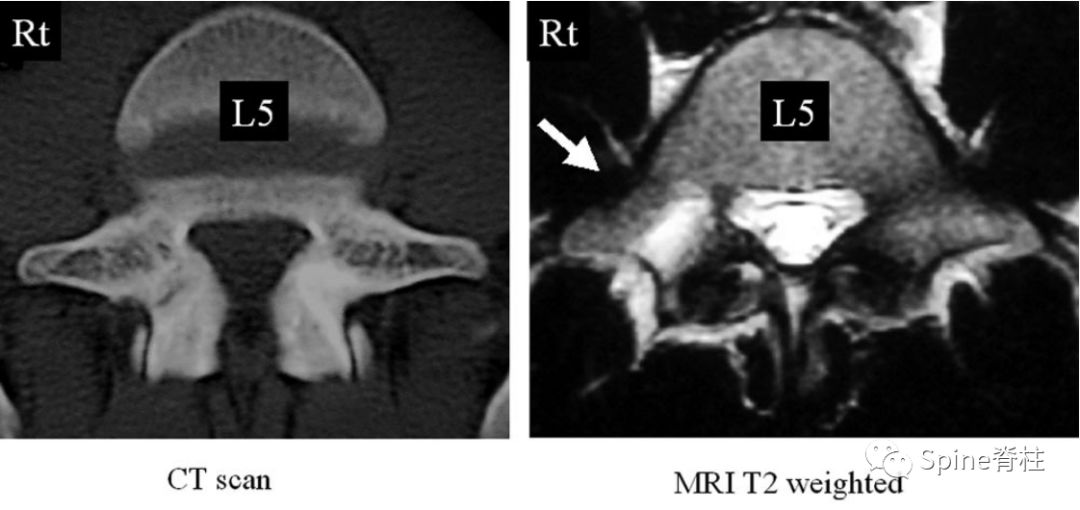

有研究发现磁共振上椎弓根出现T2高信号改变是青少年和儿童峡部裂的早期诊断征象。同时,存在椎弓根高信号改变也是保守治疗后能达到骨性愈合的良好预测指标(也就是说存在T2椎弓根右高信号改变的峡部裂患者,其峡部裂经保守治疗愈合的可能性大)

右上图为椎弓根高信号改变(+),右下图为(-)

Sairyo教授研究发现磁共振上椎弓根出现T2高信号改变是青少年和儿童峡部裂的早期诊断征象。同时,存在椎弓根高信号改变也是保守治疗后能达到骨性愈合的良好预测指标(也就是说存在T2椎弓根右高信号改变的峡部裂患者,其峡部裂经保守治疗愈合的可能性大)。

图:右上图为椎弓根高信号改变(+),右下图为(-)

右图提示椎弓根高信号改变(箭头)

右图提示双侧椎弓根高信号改变(箭头)

右图:右侧椎弓根高信号改变明显,左侧椎弓根轻微高信号

因此,Sairyo教授也提出,对于青少年腰痛患者行MRI检查时,在传统椎间盘层面的基础上(A-C线),多加一个经椎弓根层面(D线)。因为,A-C线椎间盘层面可很好看出青少年腰椎间盘突出和腰椎椎体后缘离断症,而D线经椎弓根层面可以早期诊断出腰椎峡部裂和腰椎椎弓根损伤。